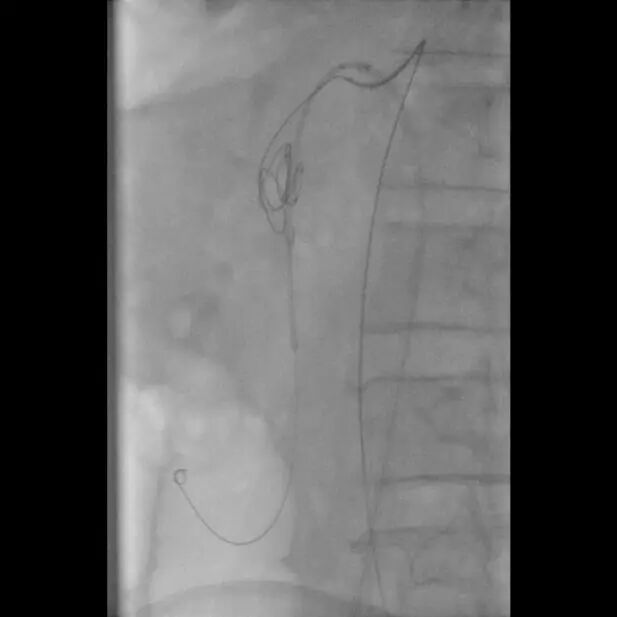

支架释放

术后造影图像

患者取仰卧位,双侧腹股沟区消毒铺单后局麻下分别经双侧股动脉穿刺置入7F(右侧)/5F(左侧)血管鞘组,予40mg肝素钠静脉注射全身肝素化,先经左股动脉插入4FRH导管,将导管头端置于肠系膜上动脉开口处,注入对比剂行肠系膜上动脉IADSA;再经右侧股动脉插入7F长鞘至肠系膜上动脉开口,旁路加压滴注生理盐水;明确病情后选取工作角度,先经4FRH导管路途下同轴送入1.7F栓塞微导管,旁路加压滴注生理盐水,经微导丝配合将其头端至于肠系膜上动脉夹层囊状动脉瘤腔内,于动脉瘤填入5枚弹簧圈行夹层动脉瘤弹簧圈填塞术;经右侧股动脉长鞘入路沿导丝送入1枚支架(SmartFlex 6mm×80mm,USA)该支架具有可预见的近端定位+参考Marker,准确定位后行肠系膜上动脉真腔成形术,支架覆盖夹层段。复行肠系膜上动脉IADSA示:支架位于肠系膜上动脉主干夹层段,支架覆盖夹层动脉瘤出入破口,支架内血流通畅,分支血管显影良好,支架以远血管主干及分支显影较术前增多增浓,多发夹层动脉瘤腔内弹簧圈均匀填塞。手术结束,使用Exoseal封堵止血系统闭合双侧股动脉穿刺点。